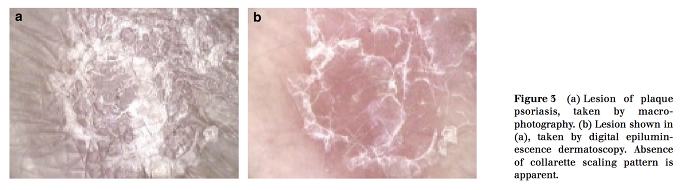

7.png

위의 사진은 같은 부위를 일반촬영한것과 digital epiluminescene dermatoscopy로 촬영했을때

장미색비강진 환부를 비교해서 보여주고 있는데요.

후자에서 보다 선명하게 테두리 부위의 명확한 collarette pattern을 보여준다는 뭐 그런 이야기 같습니다.

8.png

판상 건선에서는 윤곽 테두리만 깔끔하게 떨어지지 않고 인설이 좀 지저분하게 붙어있는 모습으로 장미색비강진과는 좀 차이를 보이네요.